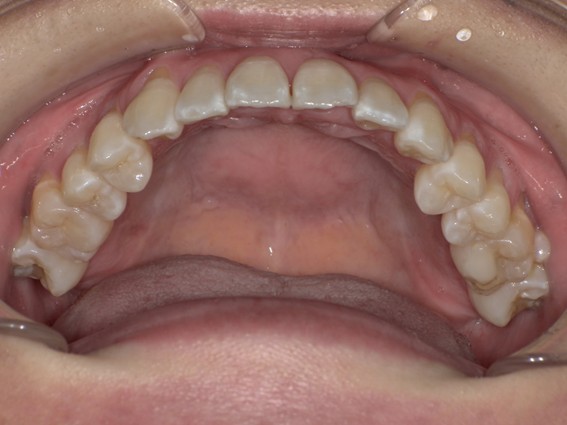

| 主訴 | 口元がでている、口が閉じずらい、上の歯と下の歯のがたつき、顎がない。 |

| 治療内容 | 上下のワイヤー矯正を行いました。 |

以前骨切りを勧められたことがあるという方でしたが、抜歯矯正で口元の突出や顎のしわを改善しました。上唇の厚みや頬の高さを考慮し、老けた印象にならないよう配慮。お顔全体のバランスと年齢に合わせた治療を行いました。